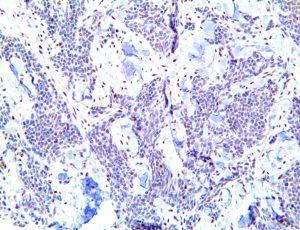

It is the ICU physician who is most likely to witness one of the deadliest manifestations of the abnormal immunological response, the cytokine storm syndrome (CSS). This response is also referred to by some as the cytokine release syndrome (CRS). CSS is characterized by continuous activation and expansion of macrophage and lymphocyte populations, which secrete large amounts of cytokines, causing the cytokine storm. This massive cytokine release is akin to hemophagocytic lymphohistiocytosis (HLH) disease, a syndrome characterized by initial unchecked and persistent activation of cytotoxic T lymphocytes and NK cells.

Clinical and laboratory manifestations of HLH include fever, enlarged liver and/or spleen, neurologic dysfunction, coagulopathy, liver dysfunction, cytopenias (i.e., low levels of erythrocytes, leukocytes, and/or platelets), hypertriglyceridemia, hyperferritinemia, hemophagocytosis, and eventually diminished NK cell activity as the immune system becomes progressively paralyzed. HLH can be familial (primary HLH) or secondary to another disease process (sHLH), such as rheumatic disease, in which it is referred to as macrophage activation syndrome (MAS, characterized by elevated ferritin).